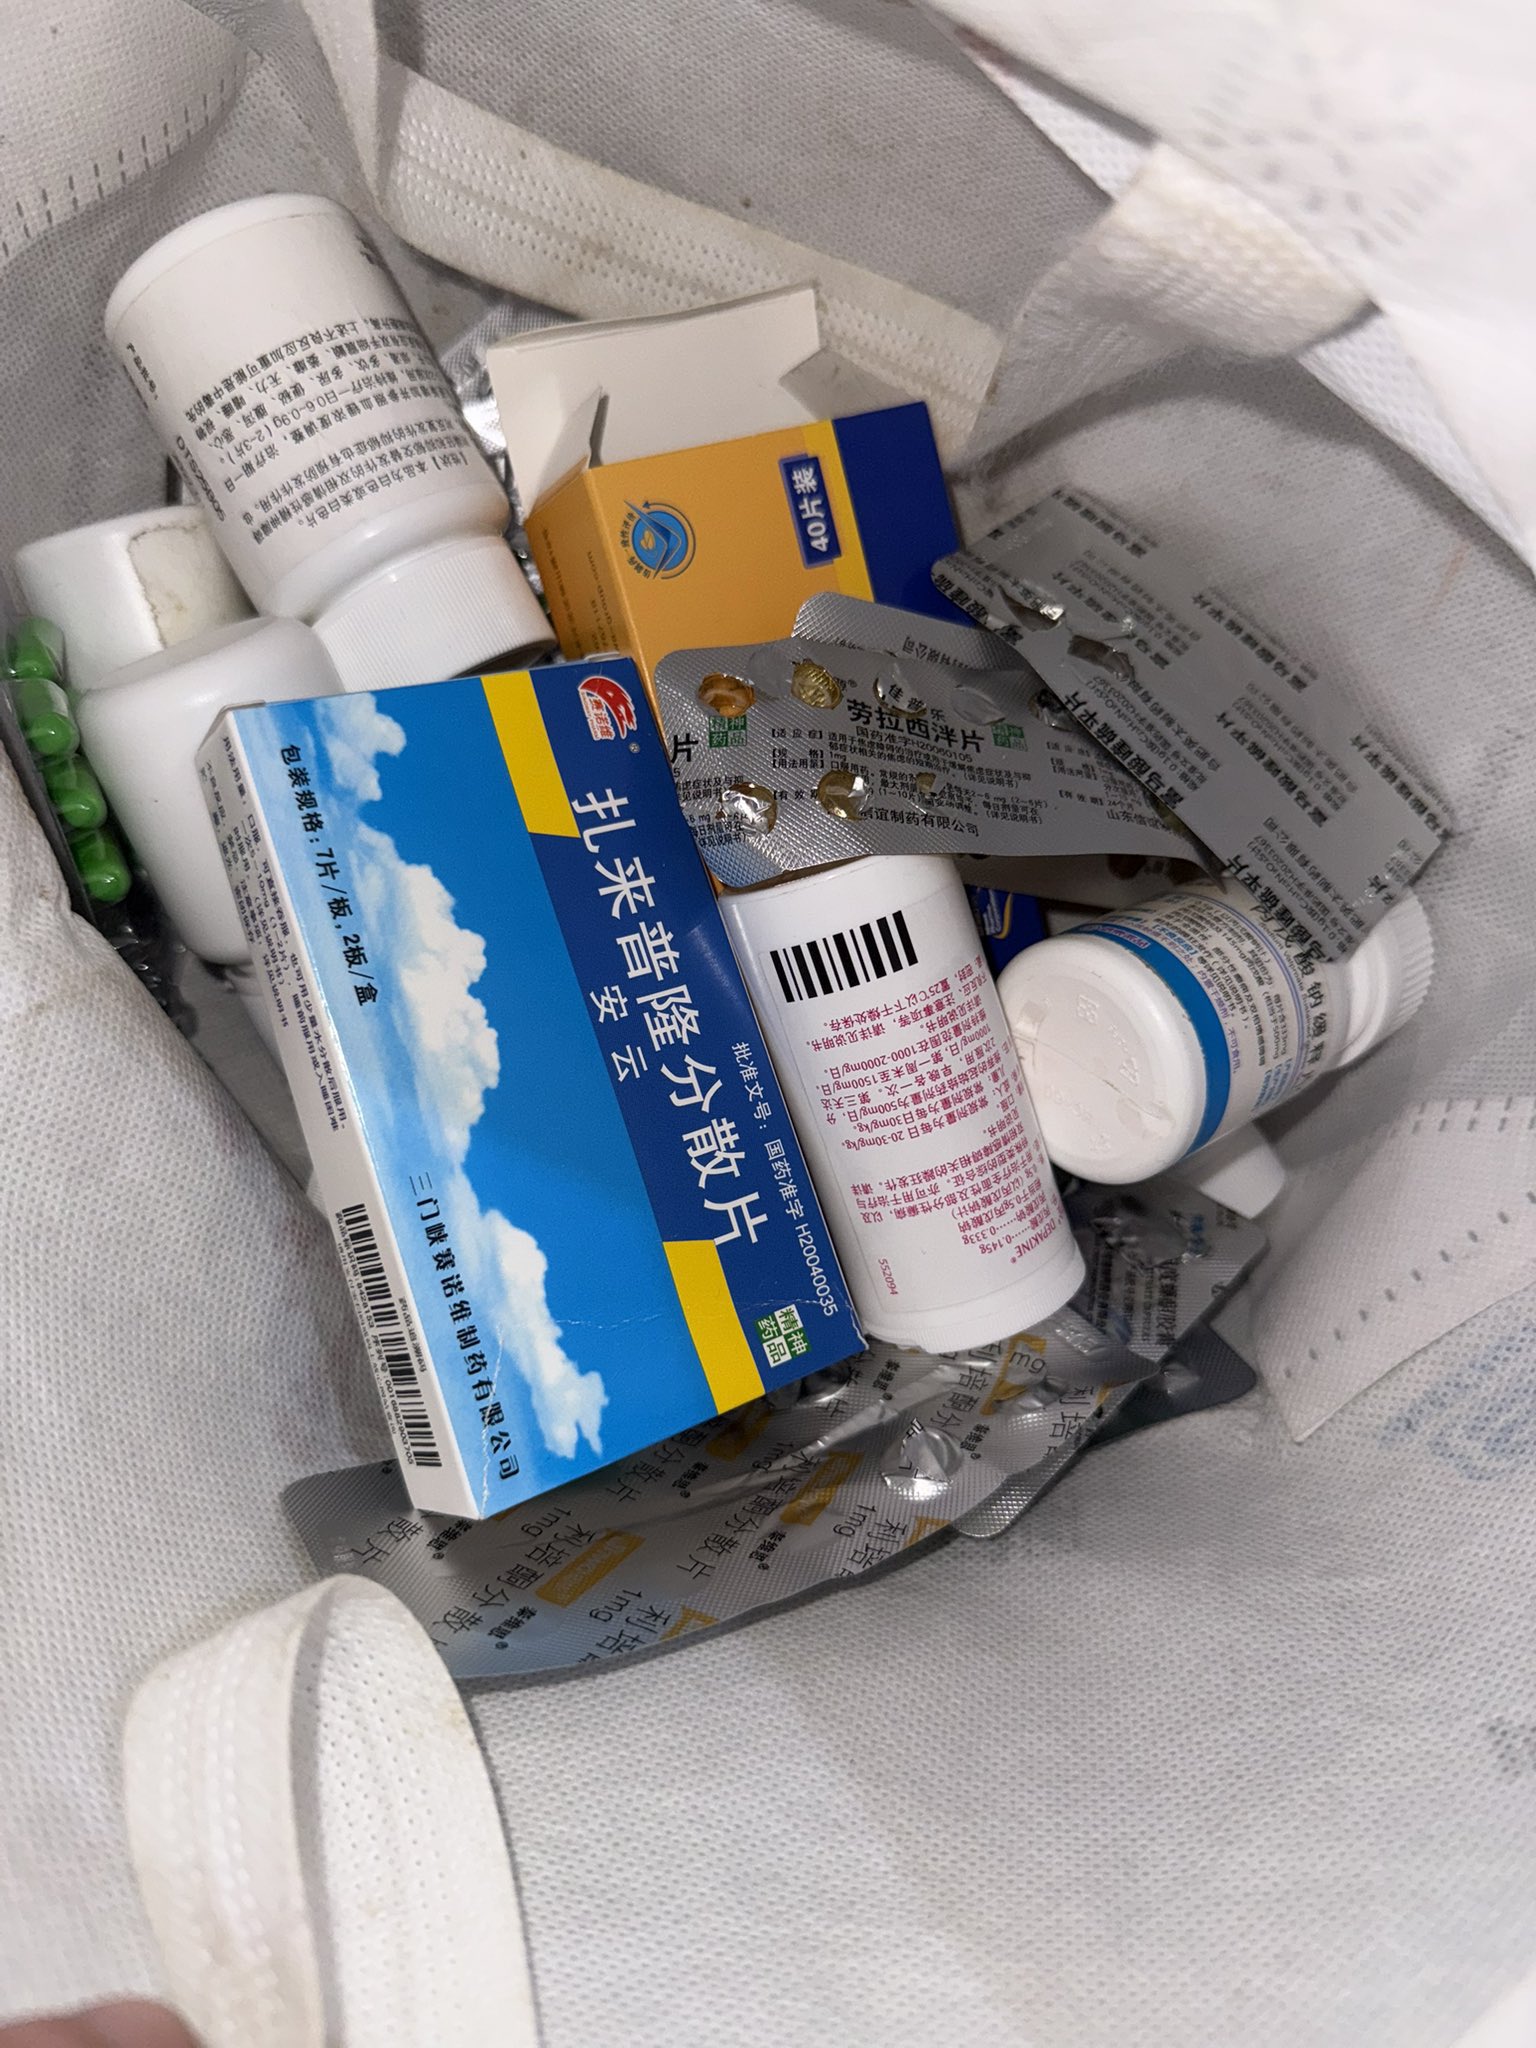

由于我现在快(痛经)痛死了,有感而发简单说说止痛药

常见NSAIDs先稍稍,首选塞来昔布,0.5-1h起效,对肠胃刺激小可以空腹服用,有中上的镇痛强度和中短的持续时间

那么有没有更强的呢🥹有,依托考昔,起效要1h以后,有着22h的长半衰期所以管一整天没什么问题,同样对胃刺激小适合我这种快痛晕过去了直接抓来吃

双氯芬酸钾起效也快适合空腹,但如果胃没那么好就可以一整个分不清哪里在痛了,所以还是垫点食物会比较好

那么再推荐一个双氯芬酸的直肠栓剂版本,直接绕过消化道刺激这关并且起效很快!